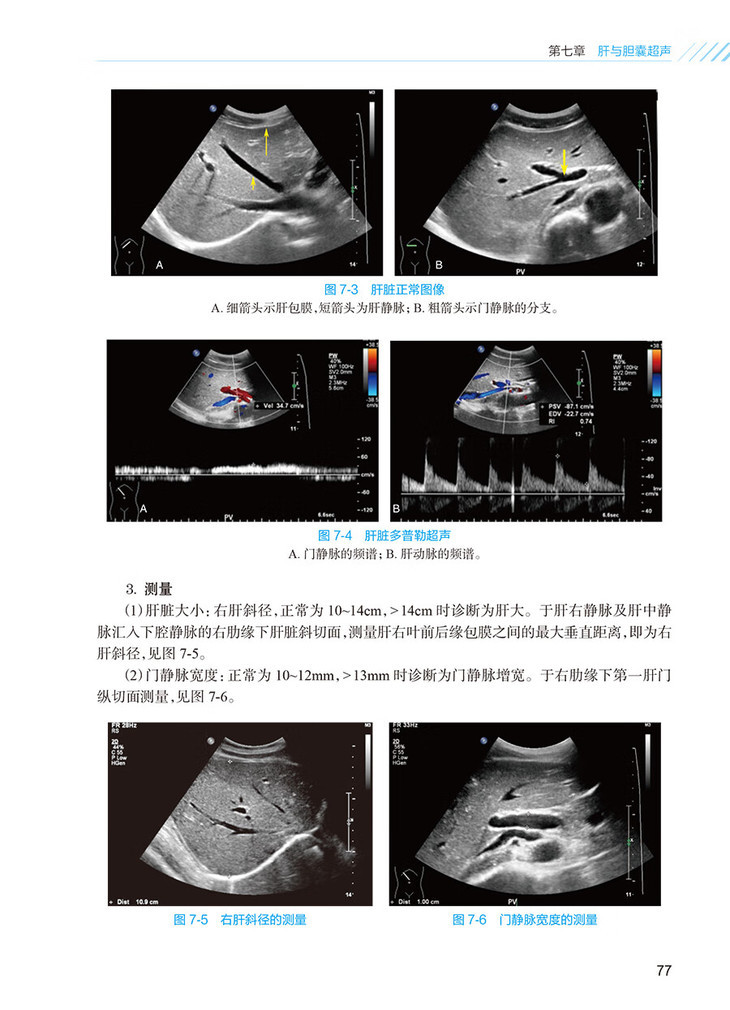

第七章肝与胆囊超声/75

第一节肝脏/75